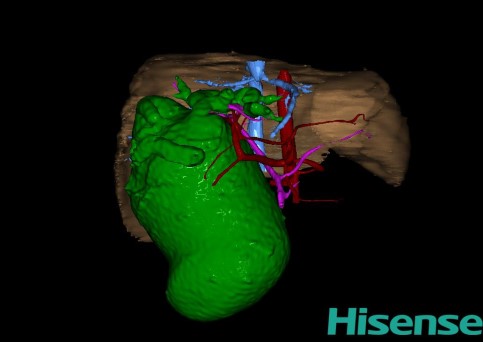

10、三维重建虚拟肝脏、胆道显像技术

三维虚拟肝脏技术是在二维影像学资料如CT等图像的基础上,通过三维重组软件和工具,比如青岛大学附属医院与海信医疗集团联合自主研发的海信计算机辅助手术系统(Hisense Computer Assisted Surgery,Hisense CAS),目前已投入临床并指导实际应用,利用该类系统对二维影像学的数据资料进行三维立体分析,重组形成立体的、有空间结构的、虚拟的肝脏三维图像。这项技术较传统的二维平面成像技术,有着明显的优势,3D虚拟肝脏技术可以构造出一个虚拟的、可视化的肝脏模型。通过对这种模型的观察,可以很容易地分辨出肝脏器官的组织结构、解剖特点,直观研究肝外胆总管的形态差异,明确肝内胆管的形态、走形、是否合并扩张、狭窄及结石,胰胆管合流的形态及共同通道内是否有狭窄、扩张和结石等病变情况,预先规划处理可能合并存在的肝内胆管扩张、狭窄或其他复杂胆道畸形,清晰地显示肝内脉管系统,包括门静脉、肝动脉及肝静脉的走行、分支,并可多角度、全方位观察病变胆道与其周围重要血管尤其是伴行的门静脉之间的解剖关系,大大提高了外科医师在术前对肝脏内部各管道结构及其变异判断的精确性和可靠性,精准地对病变进行判断和评估,还可根据患者自身的病变特点,制定出合理、个体化的手术方案,最大限度地降低术中和术后并发症发生率,并术中导航实时指导手术,提高手术的精准性和成功率。

图12:先天性胆管扩张症梭状型合并左右肝管分别汇入胆总管囊肿三维重建虚拟肝脏、胆道显像

a 图为术前二维CT图像;b 图为CT经多平面重组技术(MPR)所得的三维重建图像,可粗略地判断病变胆管的位置;c 图为MRCP显示胆总管梭状扩张;d 图为术前Hisense CAS三维重建显示胆管的分布走形及其与肝内三套血管系统的解剖关系;e 图为胆道系统立体形态及与肝脏整体的空间关系,箭头处显示对于左右肝管分别汇入胆总管囊肿中,整个肝总管也明显扩张而成为囊肿的一部分。术前规划为先将囊肿完全切除,左右肝管合并成形后再与空肠吻合。